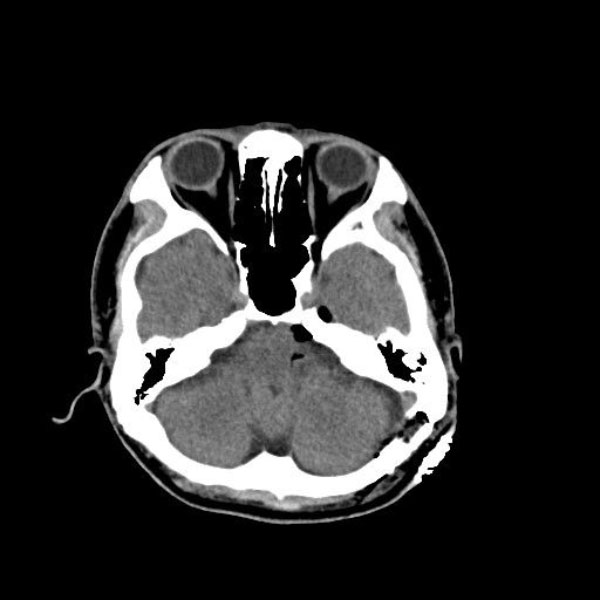

手術前

(MR1)

手術後

(CT)